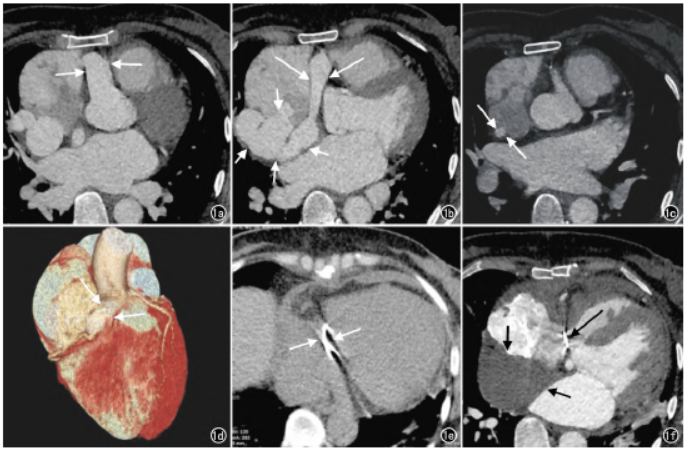

心脏及冠脉血管CT成像检查:全心增大,右冠状动脉起始段扩张增粗(图1a),于右心耳下方发出一支右冠状动脉沿右侧房室沟走行,增粗的右冠状动脉主干沿左、右心房之间走行至右侧房间沟前方、右房侧后方形成大小约4cm×6cm的瘤体(图1b),瘤体部分突出到右房并于顶端见一大小约7mm瘘口(图1c)。

图1 患者,女,48岁。a)术前冠脉CTA增强横轴面示全心增大,右冠状动脉起自右冠状动脉窦,右冠状动脉起始段窦明显扩张(箭);b)术前冠脉CTA增强横轴面示增粗的右冠状动脉窦于右心耳下方发出一支右冠状动脉沿右侧房室沟走行(长箭),增粗的右冠状动脉主干沿左、右心房之间走行至右侧房间沟前方、右房侧后方形成大小约4cm×6cm的瘤体(短箭);c)术前冠脉CTA增强横轴面示瘤体部分突出到右房并于顶端见一大小约7mm瘘口(箭);d)术前冠脉CTA三维重建图像示右冠状动脉起始段明显扩张增粗(箭);e)术后冠脉CTA平扫横轴面示右室与右心房之间可见条状高密度影,呈术后改变(箭);f)术后冠脉CTA增强横轴面示原沿右侧房室沟走行的右冠状动脉区见条状高密度影(长箭),原“右冠状动脉瘤”区(右心房后方)可见团片状低密度影,增强扫描未见强化,呈术后改变(短箭)。